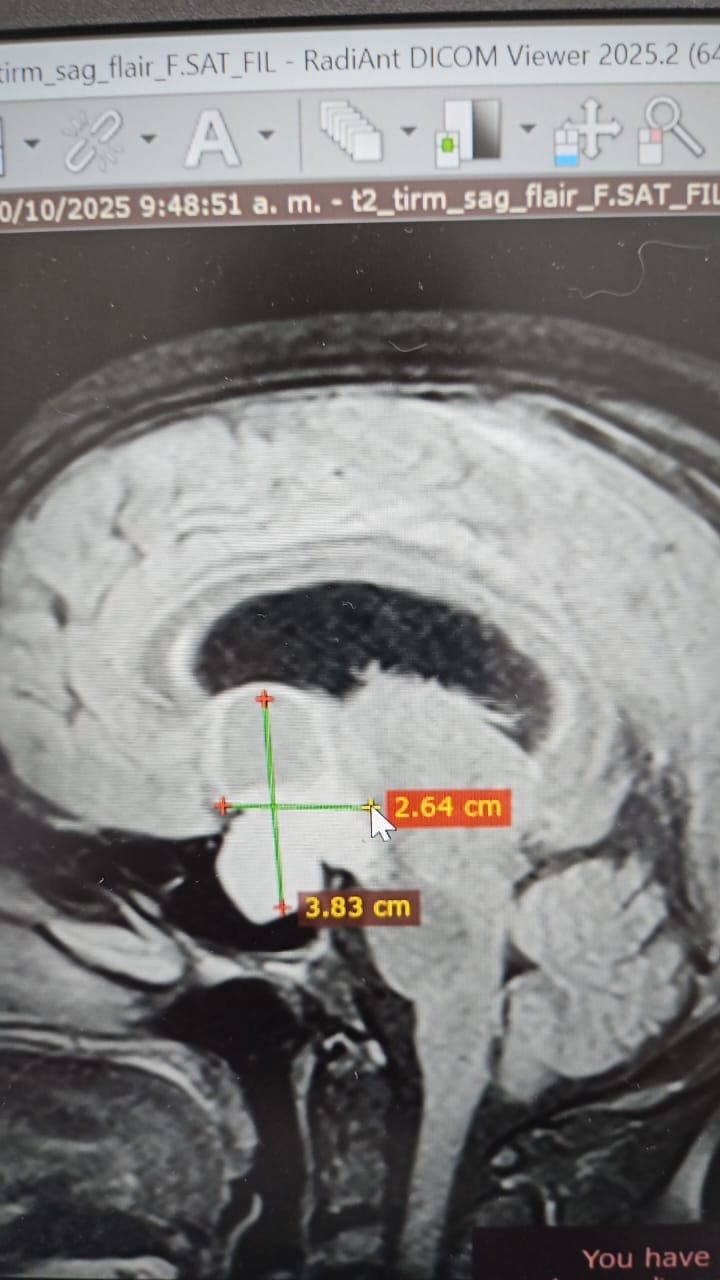

Hola, mi nombre es Yraida y estoy recaudando fondos para mi prima Ana, quien tiene varios quistes y dos tumores en el cerebro (adenoma hipofisario y craneofaringioma) y necesita una operación urgente.

Hello, my name is Yraida, and I am raising funds for my cousin Ana, who has several cysts and two brain tumors (a pituitary adenoma and a craniopharyngioma) and urgently needs surgery.